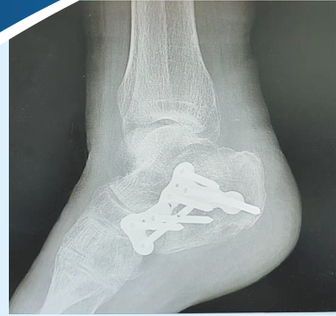

一骨折处CT扫描影像

眼见老伴摔倒后失去意识,孙老伯一时乱了方寸,连忙上前搀扶、连声呼唤。一旁的热心路人见状,主动帮忙拨打了120急救电话。大约十分钟后,救护车抵达现场,将高阿婆送往就近的第十人民医院救治。经CT检查诊断,高阿婆右侧踝关节、右侧肩关节等共三处骨折,伤情较为严重,需立即接受治疗。